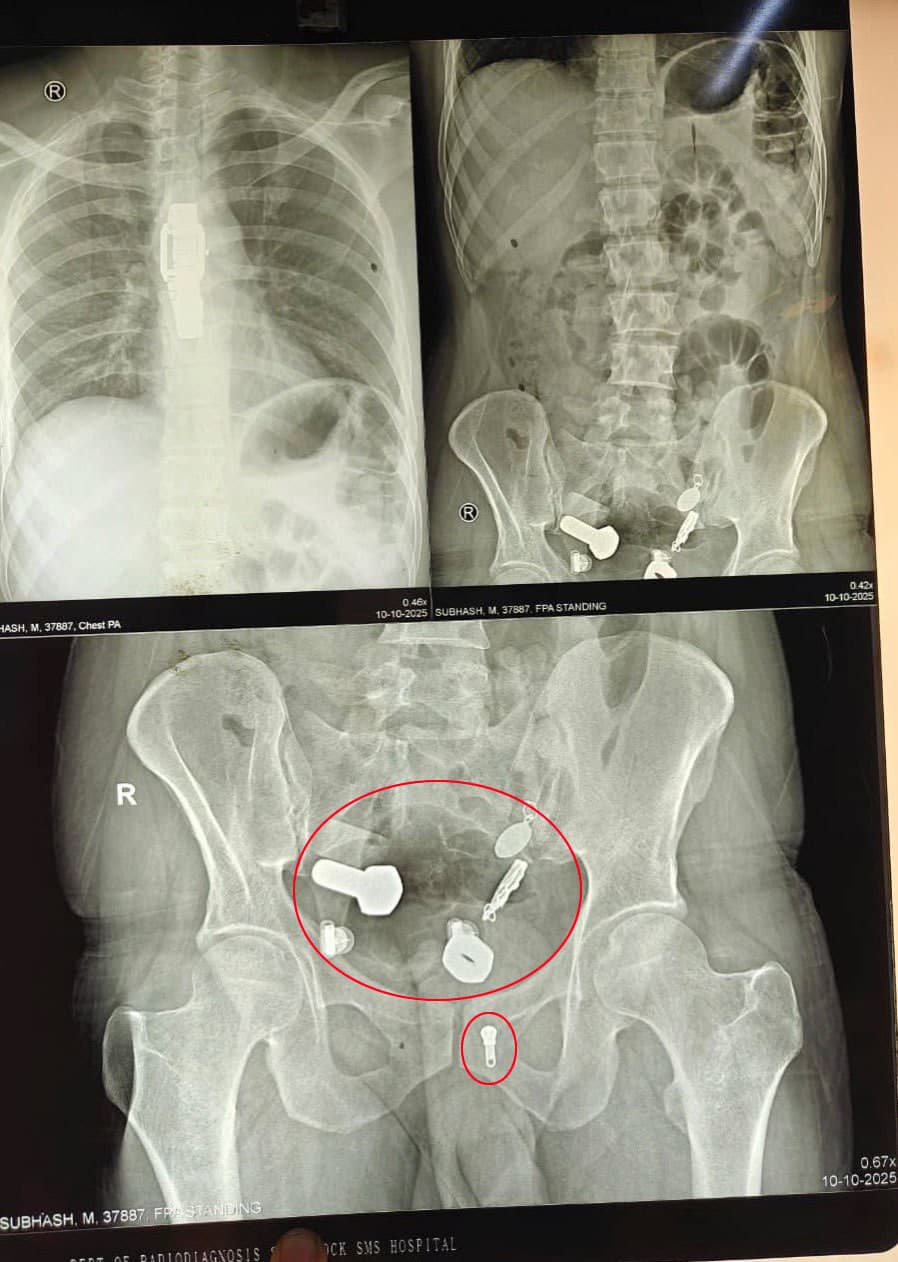

Lekári najskôr urobili röntgen a CT vyšetrenie, ktoré odhalilo, že v pažeráku pacienta uviazli náramkové hodinky, zatiaľ čo v čreve sa nachádzali kovové fragmenty, matice a skrutky. „Niečo také sme ešte nevideli,“ uviedol jeden z členov operačného tímu pre Need To Know.

Tím lekárov sa spočiatku pokúsil cudzie predmety odstrániť endoskopicky, no pre ich množstvo a ostré hrany museli pristúpiť k otvorenej operácii. Zákrok trval viac než tri hodiny.

Predmety – vrátane hodiniek – chirurgovia vybrali cez malý rez v brušnej dutine. Na záberoch z operačnej sály je vidieť, ako lekári postupne vyťahujú lesklé kovové kúsky pokryté žalúdočným obsahom.